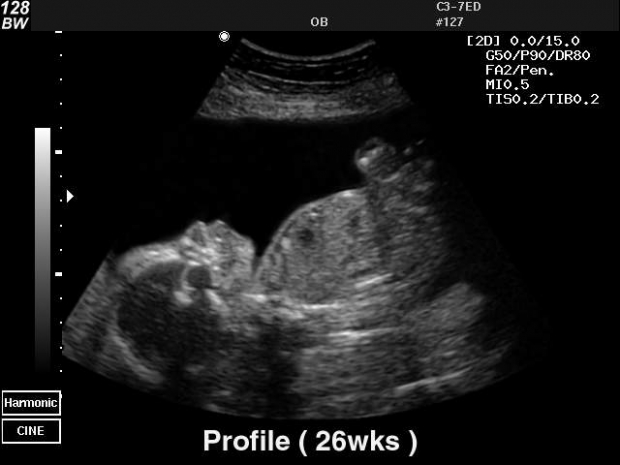

УЗИ: 26 неделя беременности

УЗИ позволяет изучить анатомию мозга плода и его лицевых структур. Вес плода составляет примерно 900 граммов. Устройство фиксирует, что глаза ребенка открыты. Тем не менее, его зрение еще не полностью развито, и он способен различать только свет и тень. Радужка глаз пока не имеет пигментации.